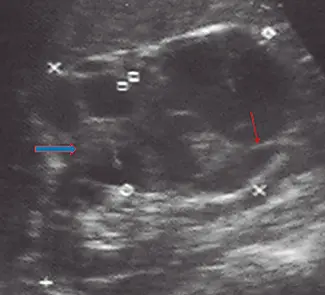

Fig: 16–a

Fig: 16–a, corte longitudinal que muestra un riñón derecho, el cual presenta un parénquima con ecos finos, homogéneos.